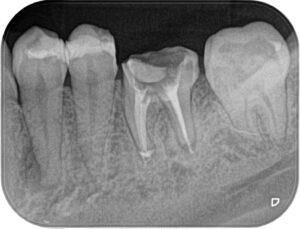

Before/After X線写真

(画像:xray_rc1.jpg 治療前後のX線比較)

治療前は根尖部に明確な透過像(感染像)が認められましたが、治療後は封鎖が確認でき、感染範囲も改善傾向にあります。